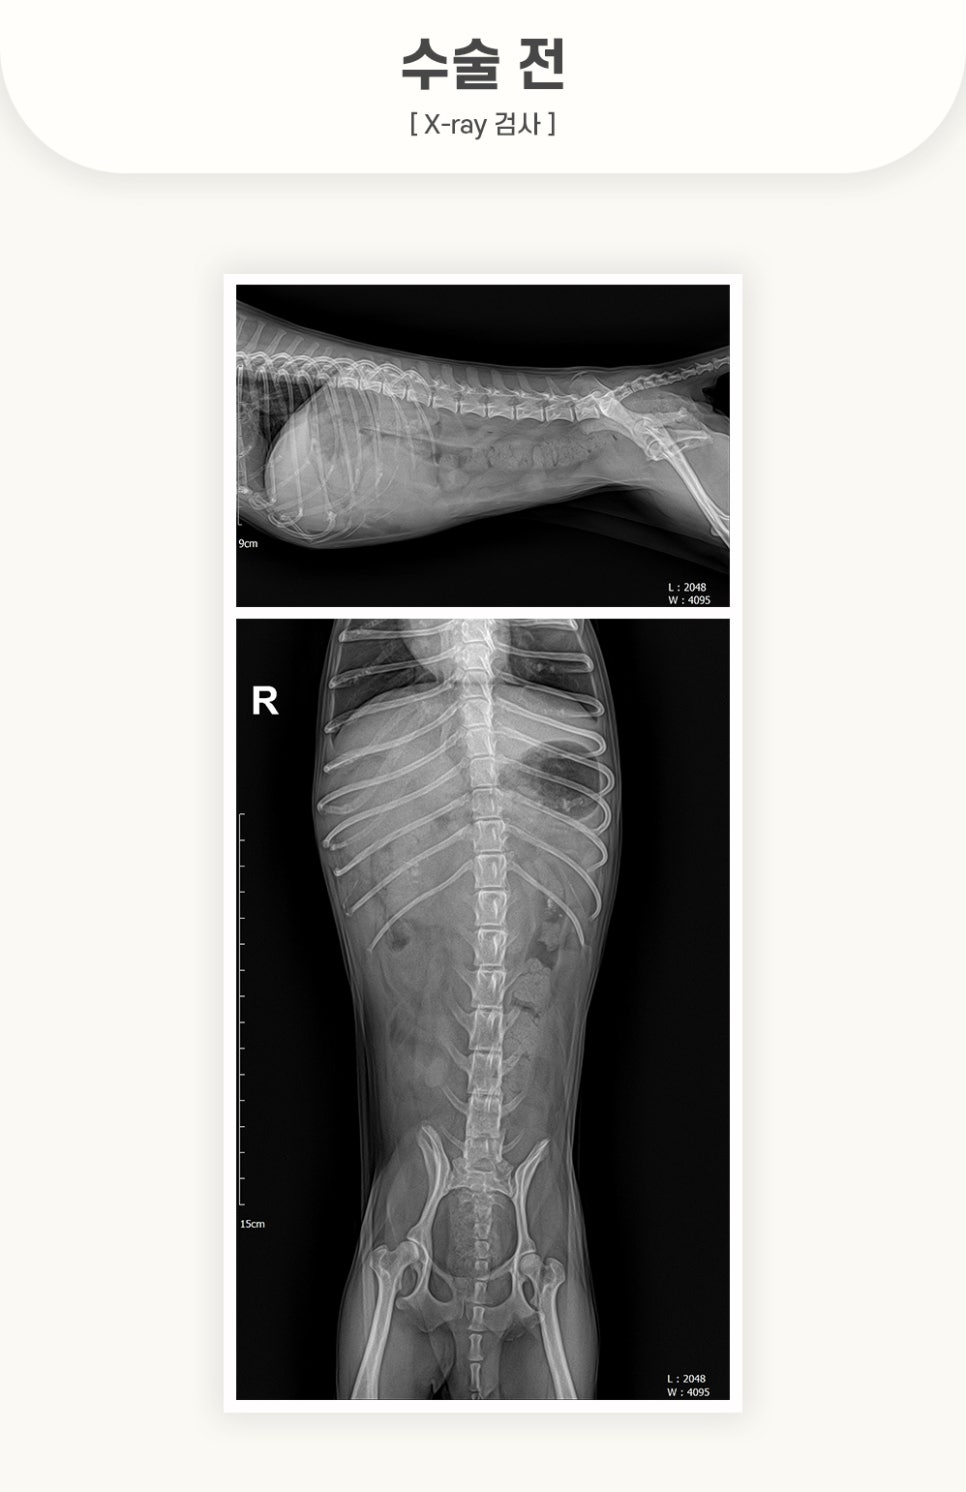

수술 전, X-ray 검사

X-ray 및 초음파 검사 진행 결과, 왼쪽 갈비뼈 아래에 위치한 비장 내 종양의 파열이 크게 의심되었습니다.